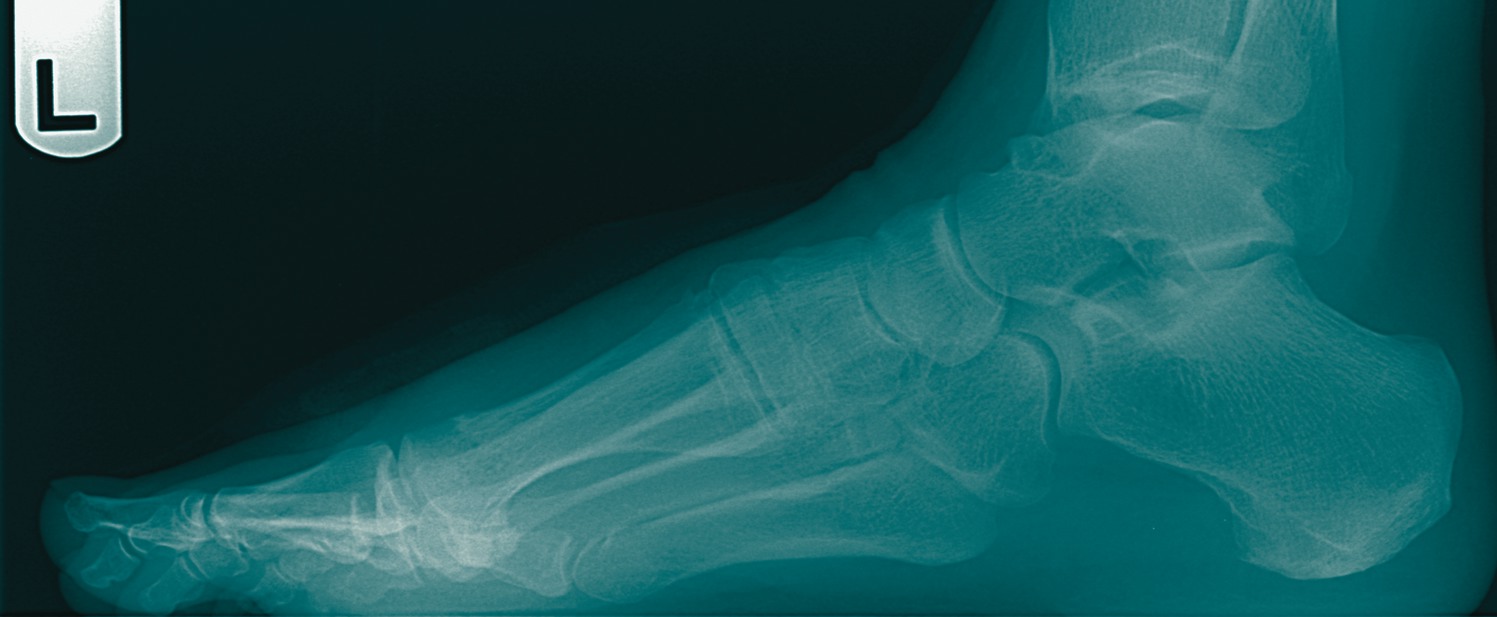

As I get more in tune with patient care, I find that the simple cases such as hallux limitus are more difficult than I initially thought because they are often more complicated and involved than the original examination might show. I have come to this conclusion after being burned by a couple of trouble cases and learning what to look for as a result. A typical patient is a 47-year-old female with chronic pain in the great toe. She has trouble in dress shoes and has mild limitation of shoegear. The patient reports having mild pain when playing golf and there is some redness of the dorsum of the foot with ambulation and activity. An examination of the region shows mild dorsal spurring and limitation of motion to 25 degrees of dorsiflexion and 20 degrees of plantar motion. She has mild dorsal pain to pressure and her end range of dorsal motion shows mild crepitus. There is no gross pain in the plantar metatarsal head and she has no medial pain and no gross stiffness or clicking of the joint. Radiographs show a very small dorsal spur. There is no gross deviation of the joint or gross arthritic changes of the joint. The patient does have mild elevatus of the first metatarsal. Although there is elevatus of the first ray on radiographs, the first ray is slightly plantar to the other rays when the patient is at rest or in a non-weightbearing position. With standing, the ray elevates due to some laxity of the first metatarsocuneiform region.